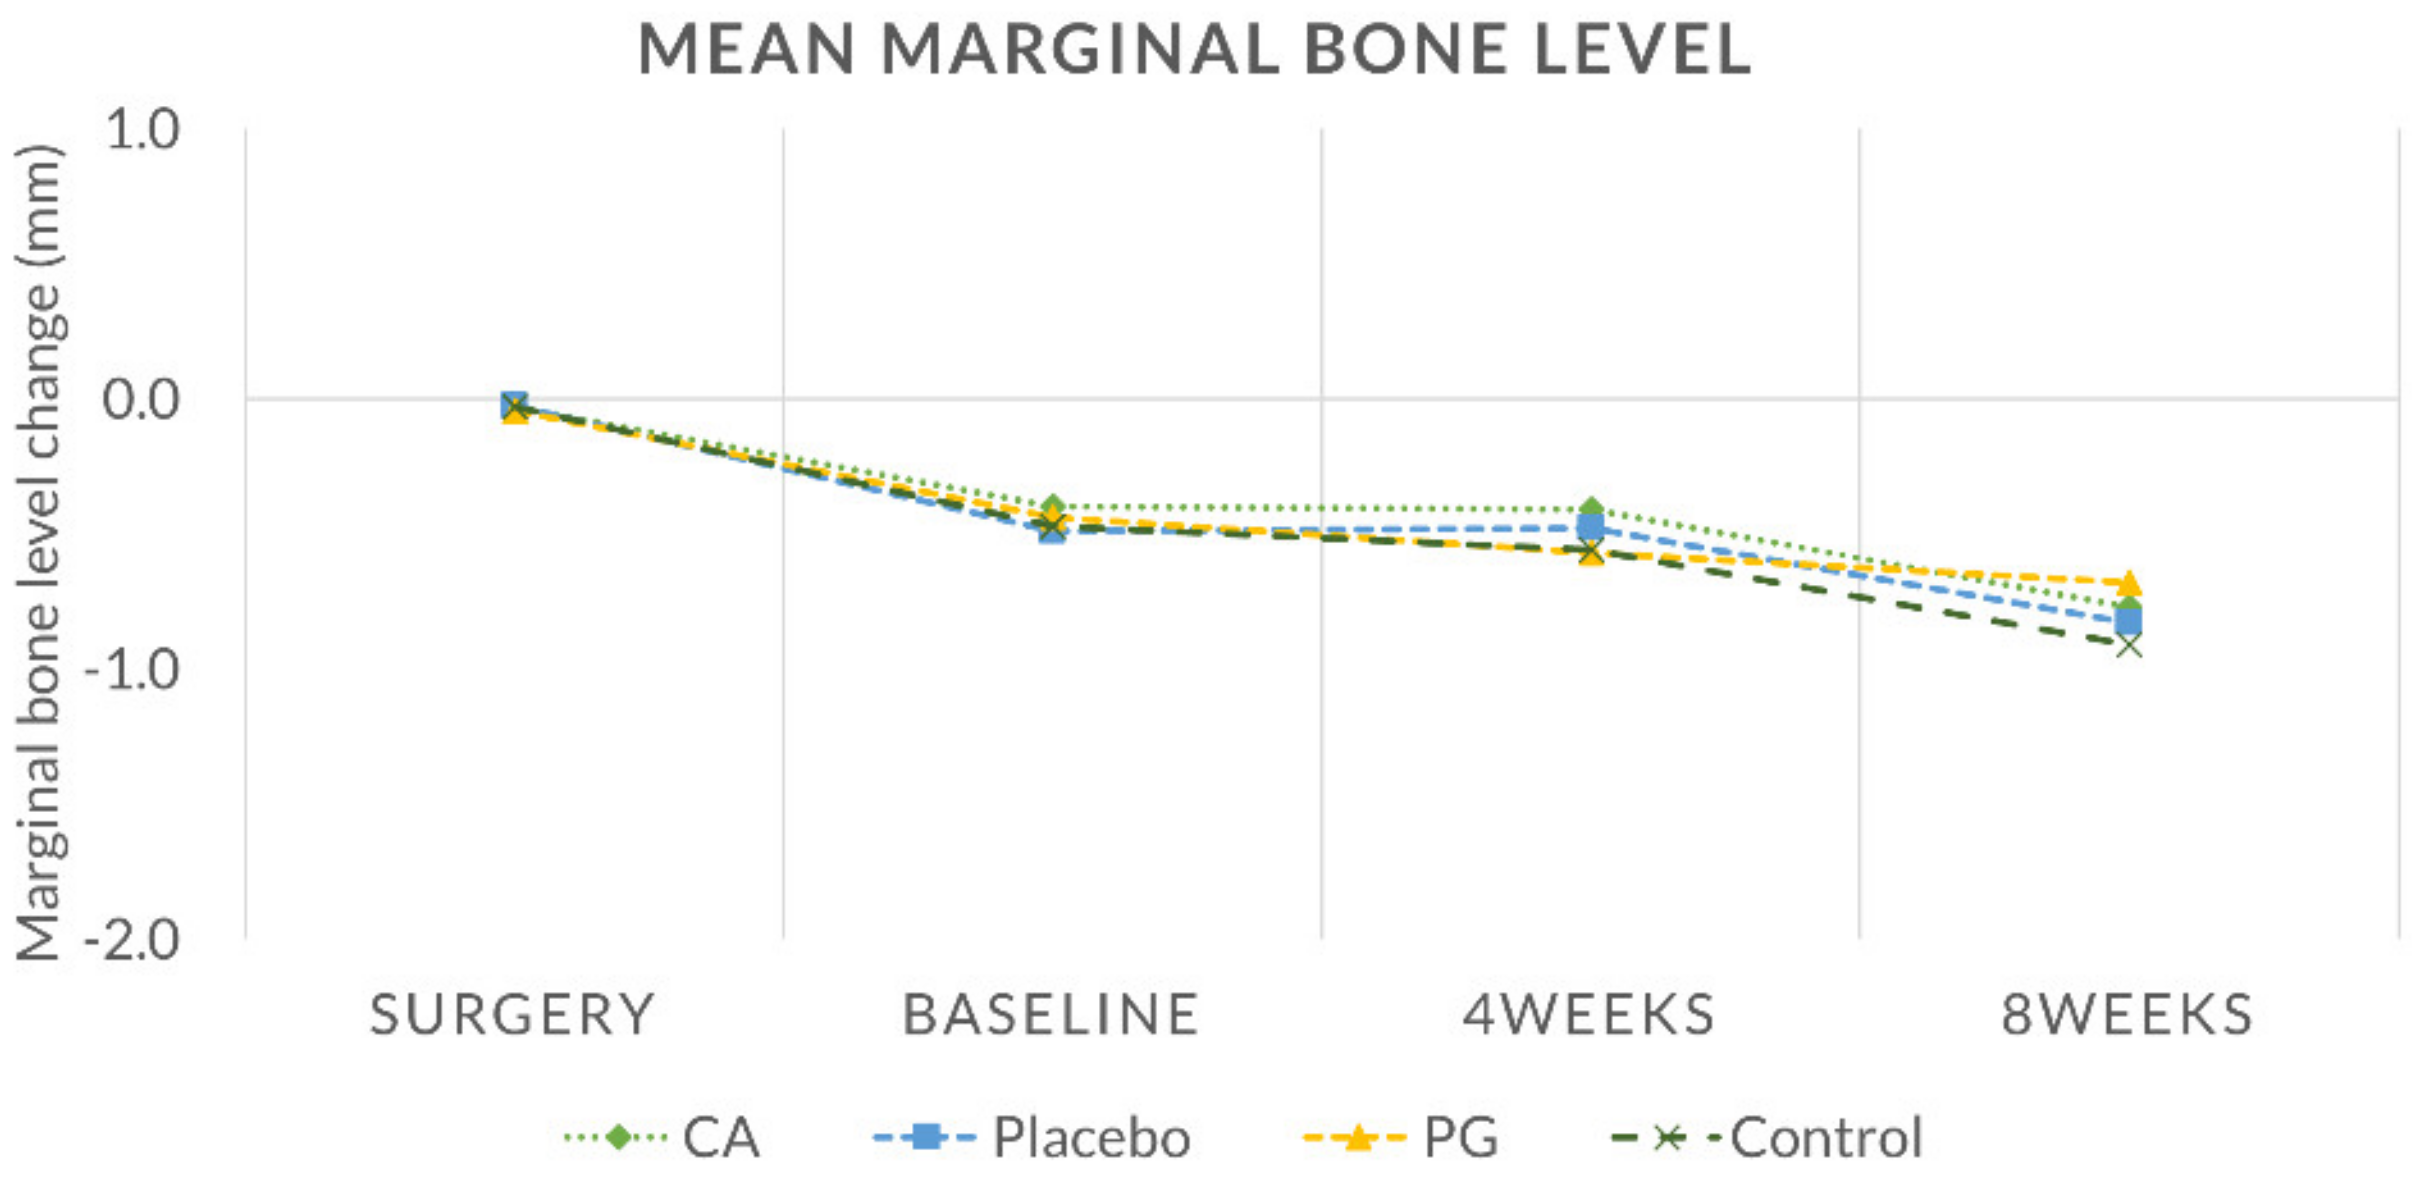

3.3. Radiographical Findings

| ΔS0–T1 | ΔT1–T2 | ΔT2–T3 | ΔT1–T3 | |

|---|---|---|---|---|

| CA | −0.38 ± 0.26 | −0.01 ± 0.20 | −0.36 ± 0.29 | −0.37 ± 0.26 |

| Placebo | −0.47 ± 0.30 | 0.01 ± 0.02 | −0.35 ± 0.24 | −0.34 ± 0.23 |

| PG | −0.39 ± 0.38 | −0.14 ± 0.17 | −0.11 ± 0.15 | −0.25 ± 0.23 |

| Control | −0.44 ± 0.30 | −0.09 ± 0.18 | −0.35 ± 0.26 | −0.44 ± 0.29 |

| p-value | 0.813 | 0.439 | 0.181 | 0.590 |